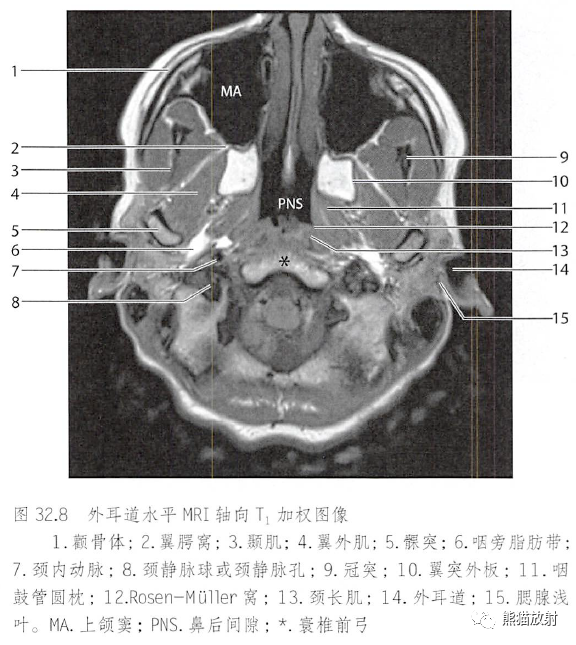

冠状面mri t1wi,各图中箭所示均为颞下窝图4-9 颞下窝图4-9a.